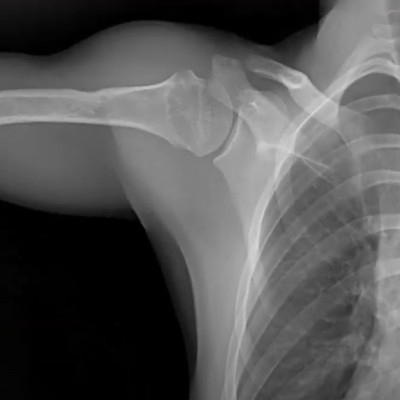

Musculoskeletal & Orthopedic Applications

DDR transforms orthopedic diagnostics by presenting bone and soft tissue in motion. Unlike static X-rays, DDR allows orthopedists to visualize joint stability and kinematics in weight-bearing positions. This is critical for diagnosing whiplash, impingement syndromes, and ligament instability.

Upper Extremities